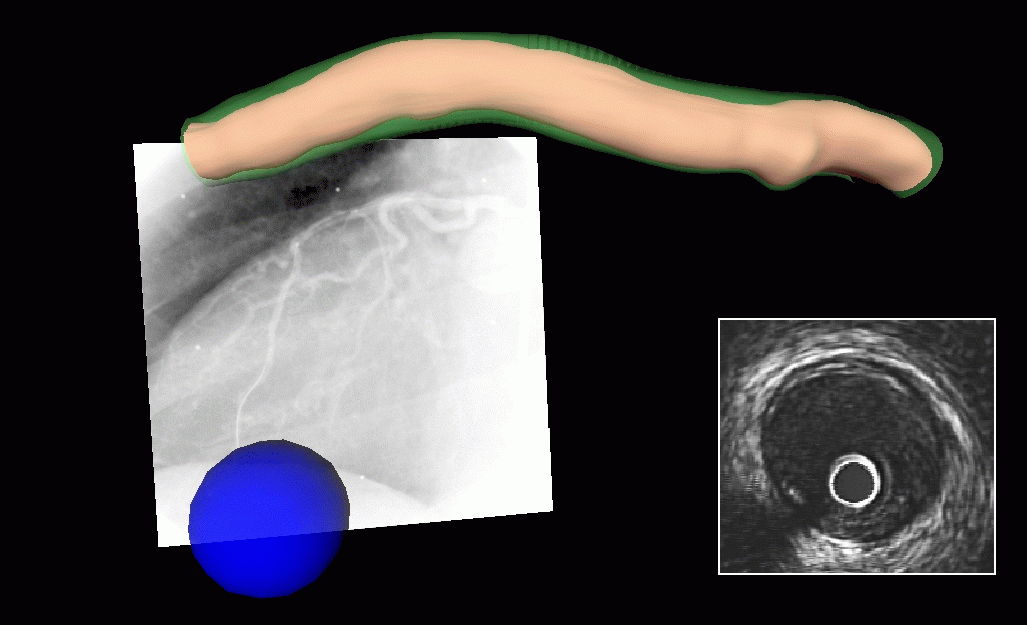

3-D Scene Showing Lumen and Adventitia Contours